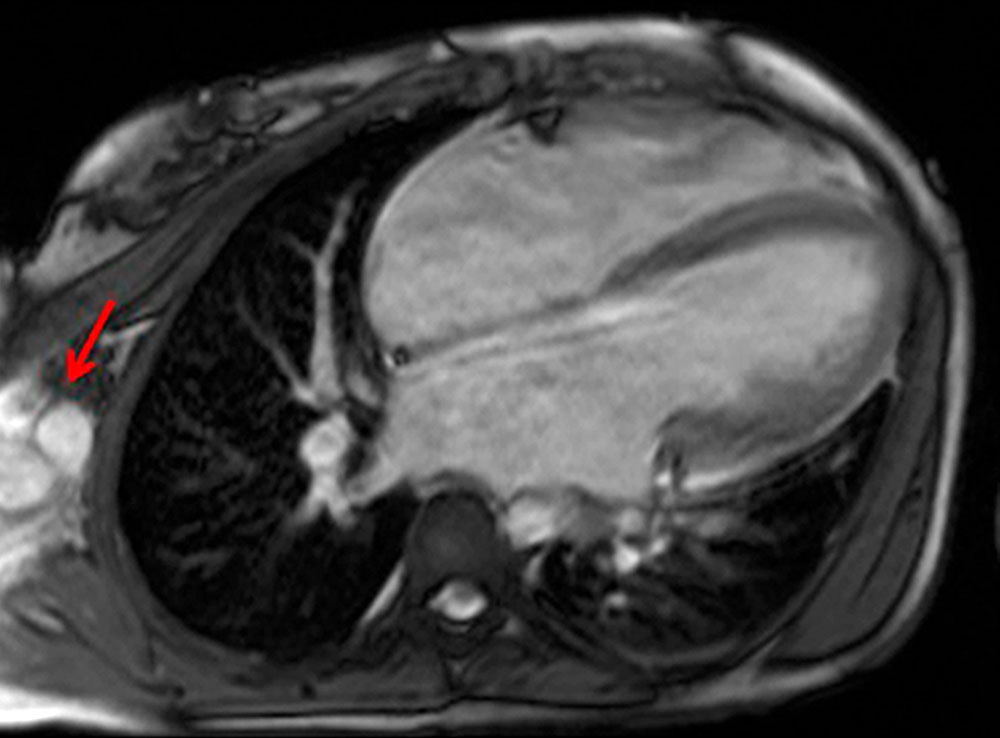

In Abhängigkeit von Angioarchitektur und Lokalisation können Blutungen, Ulcera und gangränöse Veränderungen auftreten. Kardiale Symptome treten entweder direkt nanch der Geburt oder erst in den fortgeschrittenen Krankheitsstadien in Erscheinung (Tachyarrhythmie, linksventrikuläre Hypertrophie und Dilatation).

• Herz: Tachykardie, Tachyarrhythmie, Kardiomegalie, Dilatation oder Hypertrophie, high-output cardiac failure